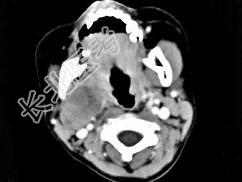

- 单项选择题女,4岁, 右侧颈部可扪及一包块约两个月,无热无痛, CT如图所示,最可能的诊断为  (    )